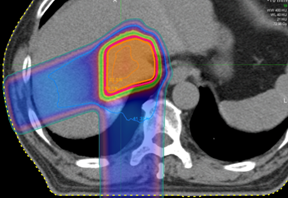

肝臓癌に対する陽子線治療の線量分布

腫瘍に線量を集中して、正常の肝臓のダメージを低減した治療が可能です。